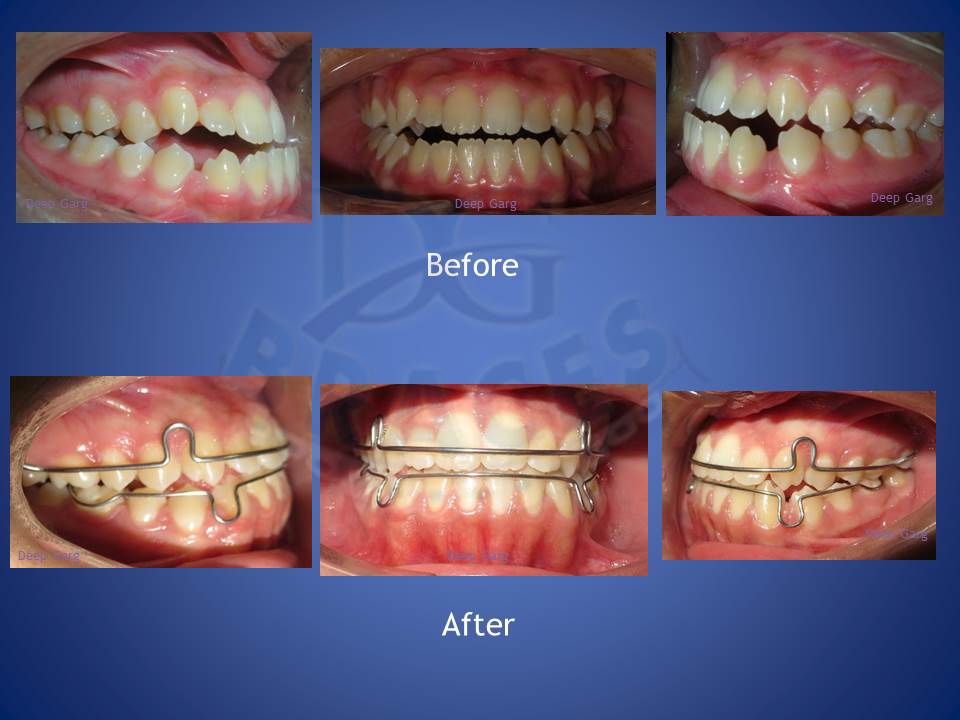

6.Lower jaw when forward can be corrected with the help of reverse pull head gear when treated at young age of 12-14 in boys and 10-12 yrs in girls. excellent result achieved here!!!